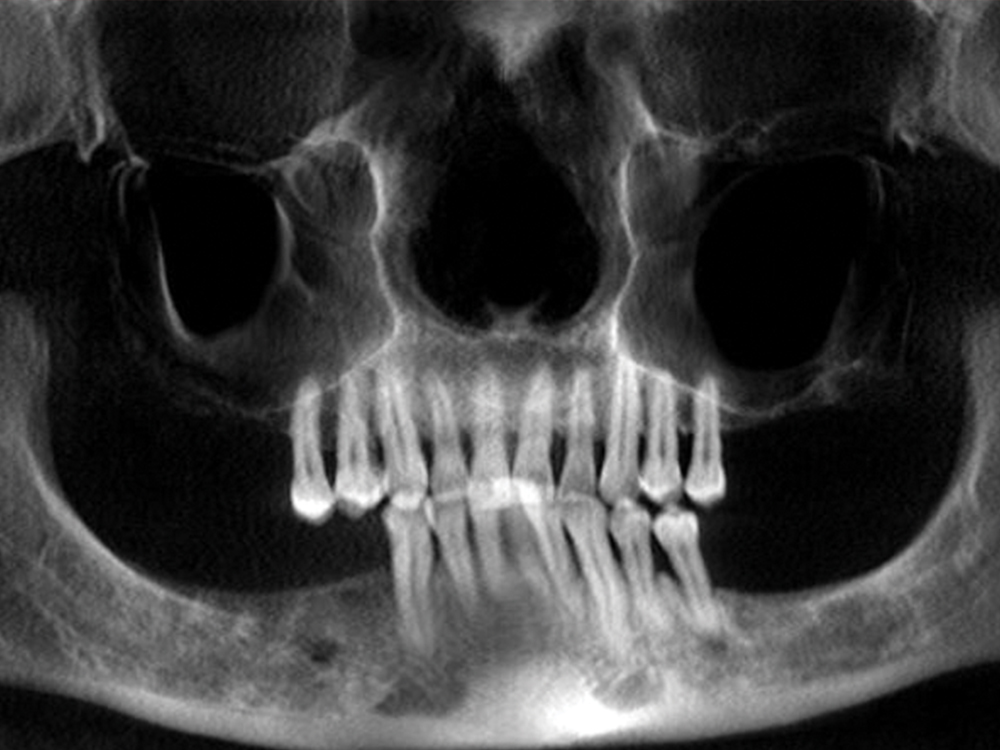

Dr. Fish recently placed five mandibular implants for a patient who requested a permanent solution for terminal dentition. He opted to place and immediately load five Hahn Tapered Implants with a fixed provisional denture. After the implant sites healed, Hahn Multi-Unit Abutments were connected to the implants and elevated the restorative platform above the soft tissue, thereby simplifying the fabrication of the immediate provisional denture as well as the final restoration.

Prior to the surgical appointment, we had a temporary denture specifically made for conversion to a fixed appliance after placing implants. We took out his remaining lower teeth and immediately placed five Hahn™ Tapered Implants (Glidewell; Irvine, Calif.). I positioned the three anterior implants axially, and I angled the posterior implants mesially to avoid the inferior alveolar canal. I freehanded the surgical procedure, and it came out really well. We connected three straight multi-unit abutments to the anterior implants and two angled 17-degree multi-unit abutments to the posterior implants. Then, we prepared holes in the denture, did the pickup procedure with the temporary cylinders, reshaped it, and sent him home with the fixed, converted denture in place. This was my first immediate load fixed full-arch restoration on multi-unit abutments. As I mentioned earlier, this was a procedure I learned at Dr. Patel’s course at Glidewell. It was something I took home with me and was able to put it into practice within a few weeks. The patient is kind of a quiet guy, but it was obvious that he was really happy to leave there with fixed teeth.